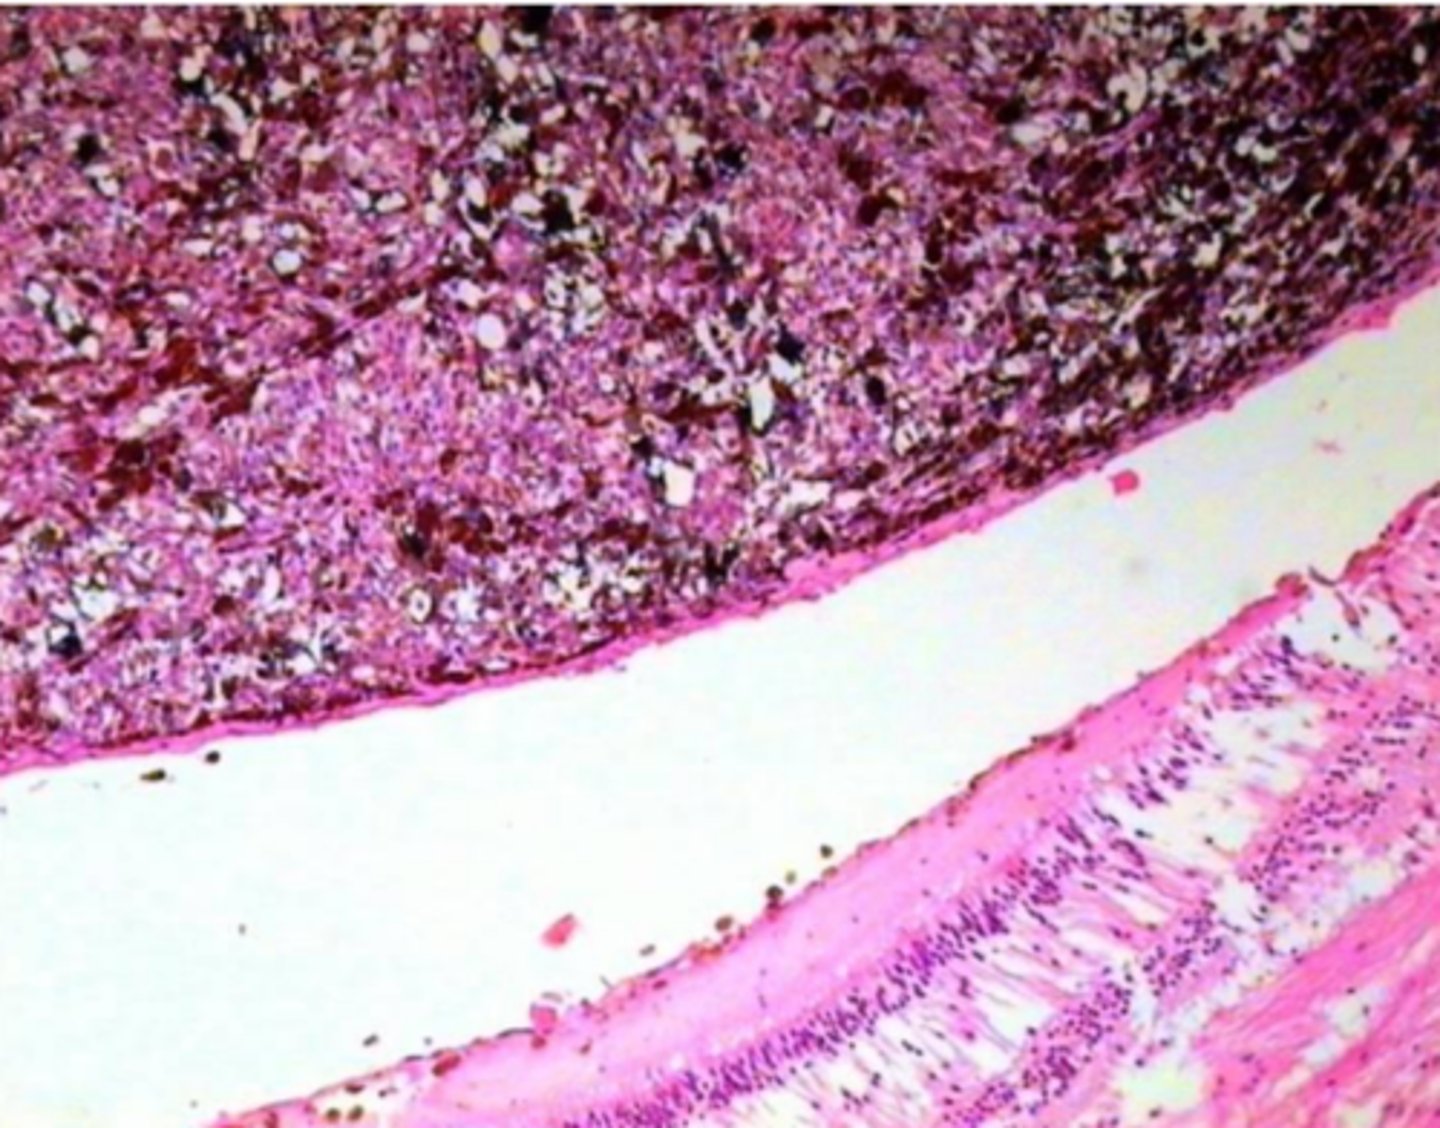

Melanomas metastāze zarnas sieniņā

11